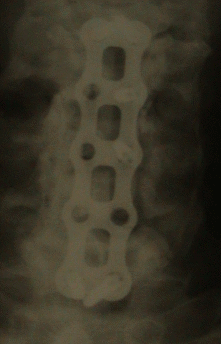

21-JUNE-2006 KHALEEL RASHID HMAMY 72 YEARS SEVERE CCS WITH OPLL AND COMPRESSION AT C3-4, C4-5 AND C5-6 LEVELS.

Through anterior approach corporectomy of C4-5-6 was done and the hypertrophied OPLL was removed. A small bridge was left  intentionally in the C4 body about 7 mm height and 3 mm thickness to prevent slipping of the 55 mm length remolded fibular graft harvested from the right leg.  The graft was reconstructed to have some curvature resembling the curvature of the Hybrid Reflex cervical plate and first a 4 level 58 mm length was used and the fibular graft was attached to it by 2 screws  10 mm length.

The graft filled exactly the gap, but a problem came with screw fixation, since he had previous surgery and the fused and hypertrophied  and calcified anterior longitudinal ligament. Control images showed unacceptable alignment, for what it was necessary to remove the device and de novo use 78 mm length plate  and the construct with traction and additional remolding got acceptable position and acceptable screw fixation between C3 and C7.

1. The patient operation took 8 hours. 4 hours of them to repeat the insertion of the construct, to be acceptable as seen in the below figures. If you see that, the construct is not satisfactory, do not hesitate to change it even it needs further efforts. It seems that, the artistic touch with engineering capabilities must be considered in such surgeries.

Cervical X-ray: AP view   Cervical X-ray: Lateral view.

22-June-2006 Postoperative control cervical X-ray showing the construct and the fibular graft.